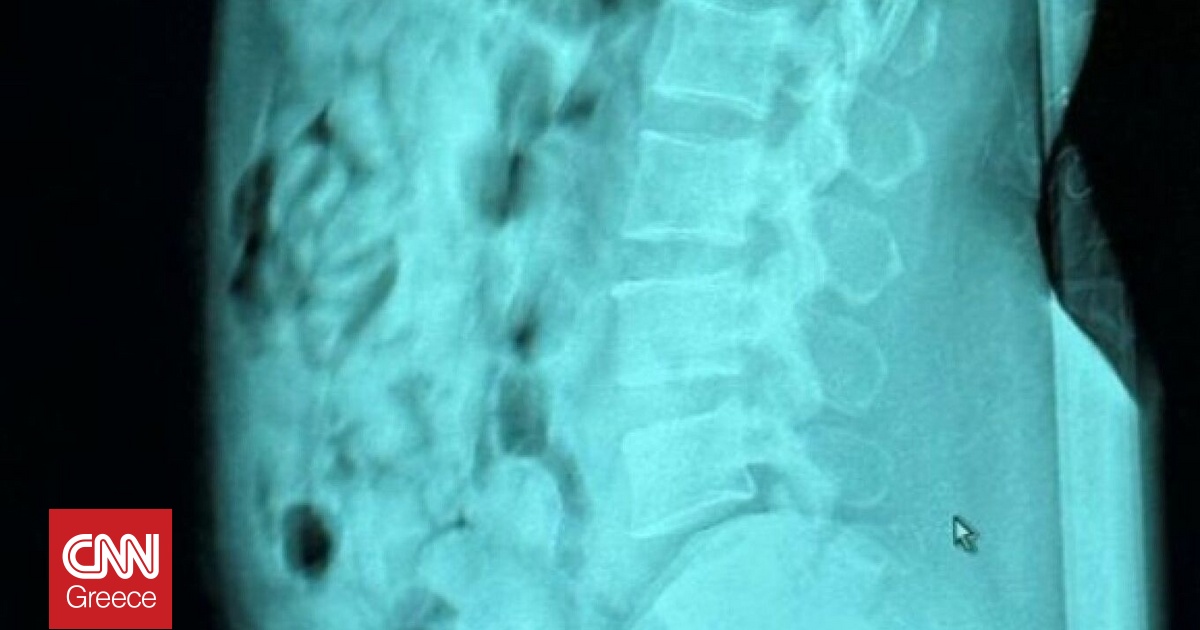

Στην επ’ αυτοφόρω σύλληψη μιας 46χρονης γυναίκας από την Νιγηρία, η οποία είχε καταπιεί 120 αμπούλες ηρωίνης συνολικού βάρους 1.393 γραμμαρίων, προχώρησαν οι ιταλικές αρχές στο αεροδρόμιο Orio al Serio του Μπέργκαμο.

Η γυναίκα από τη Νιγηρία, που εργαζόταν ως πλανόδια πωλήτρια και ζούσε στην Ιταλία από το 2013, συνελήφθη από στρατιώτες της Guardia di Finanza και υπαλλήλους της Τελωνειακής Υπηρεσίας στο αεροδρόμιο του Μπέργκαμο, έπειτα από…